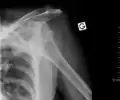

A shoulder dislocation often occurs as a result of a fall onto an outstretched arm or onto the shoulder.[3] Diagnosis is typically based on symptoms and confirmed by X-rays.[2] They are classified as anterior, posterior, inferior, and superior with most being anterior.[2][1]

A diagnosis of shoulder dislocation is often suspected based on the person's history and physical examination. Radiographs are made to confirm the diagnosis. Most dislocations are apparent on radiographs showing incongruence of the glenohumeral joint. Posterior dislocations may be hard to detect on standard AP radiographs, but are more readily detected on other views. After reduction, radiographs are usually repeated to confirm successful reduction and to detect bone damage. After repeated shoulder dislocations, an MRI scan may be used to assess soft tissue damage. In regards to recurrent dislocations, the apprehension test (anterior instability) and sulcus sign (inferior instability) are useful methods for determining predisposition to future dislocation.

Anterior dislocation of the right shoulder. AP X ray